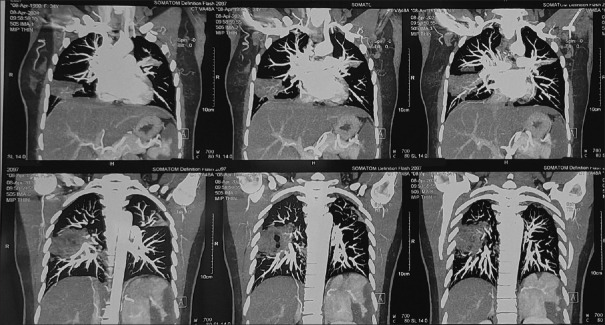

Tuberculosis (TB) continues to be a major global health concern, particularly in regions where it is endemic. While TB commonly affects the lungs and extrapulmonary sites, its presentation as vasculitis leading to multiple organ infarcts is an extremely rare phenomenon. This case report describes a 34-year-old female who developed simultaneous infarctions in the spleen, kidney, and lungs due to TB-related vasculitis. The diagnosis was established through clinical presentation, imaging studies, and confirmation of Mycobacterium tuberculosis via sputum CBNAAT. The patient was successfully managed with antitubercular therapy (ATT) and corticosteroids, demonstrating significant clinical improvement. The rarity of multisystem infarcts caused by TB underscores the importance of considering tuberculous vasculitis in the differential diagnosis of unexplained infarcts, particularly in endemic regions. Early detection and timely intervention are crucial in preventing severe complications and improving patient outcomes.